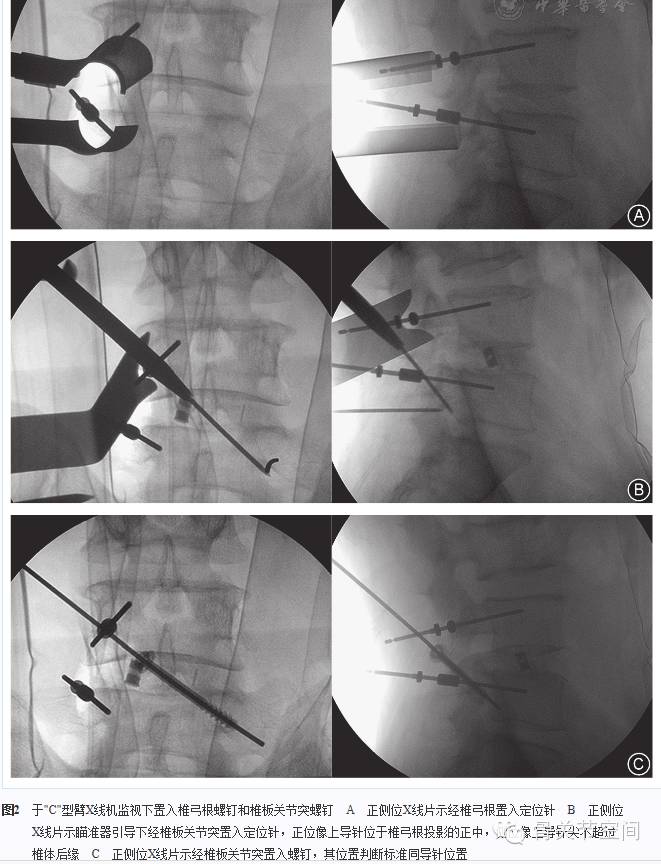

全身麻醉,患者俯卧位。以病变节段为中心,取有神经根症状侧或病变严重侧旁开棘突约2~3 cm纵行切口。锐性切开腰背筋膜,于多裂肌肌纤维间用手指钝性分离,直达椎板和关节突表面。插入扩张套管,逐级扩张,置入带光源的通道(图1),使其底部呈喇叭状张口,将通道保持外倾及头倾方向固定。清除椎板、关节突表面残余软组织,充分显露椎板间隙及关节突关节,经"C"型臂X线机透视确定病变节段。

在我们自行设计的瞄准器(专利号:ZL 2009 2 0120264.5)[23]引导下于对侧置入椎板关节突螺钉[19,24,25],单节段置入一枚,双节段置入两枚。取出椎弓根定位针,分别置入螺钉(单节段病变置入两枚,双节段病变置入三枚),安装钛棒并适当进行椎间压缩。置钉操作均在"C"型臂X线机监视下完成(图2)。